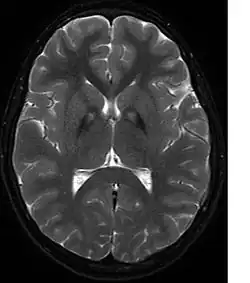

Rozpoznanie opiera się na badaniu MRI mózgu T2-zależnym, wykazujące charakterystyczne zmiany hiperintensywne w przednioprzyśrodkowej części gałki bladej i obniżenie sygnału z zewnętrznej warstwy gałki bladej i części siatkowatej istoty czarnej[2], tzw. objaw tygrysiego oka, charakterystyczny, ale nie patognomoniczny dla choroby Hallervordena-Spatza[3]. Badanie neuropatologiczne wykazuje obecność złogów żelaza i α-synukleinododatnich sferoidów w gałce bladej.